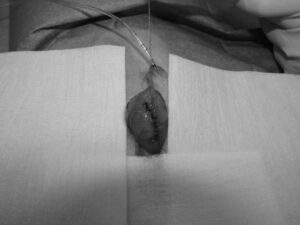

ワンちゃんが乳腺にできた複数のシコリを気にされて来院されました。bilateral mastectomyで対応しました。摘出後の病理組織検査の結果は、「R3-4間腫瘤:乳腺癌(複合型)」でそれ以外は「良性乳腺混合腫瘍」でした。無事元気に退院し、その後再発もなく経過は良好です。よかったね。